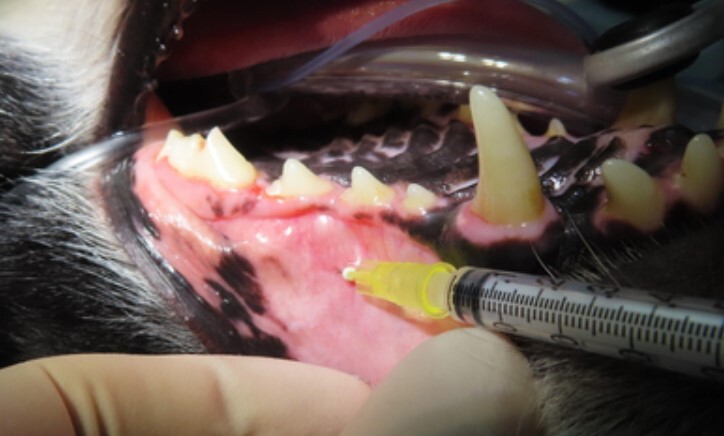

해당 치아에 국소 마취를 적용 후 치료를 진행합니다.

신경 전체를 제거하는 신경치료 대비 불필요한 신경 치료를 줄일 수 있고 치료 시간이 짧은 장점이 있습니다.